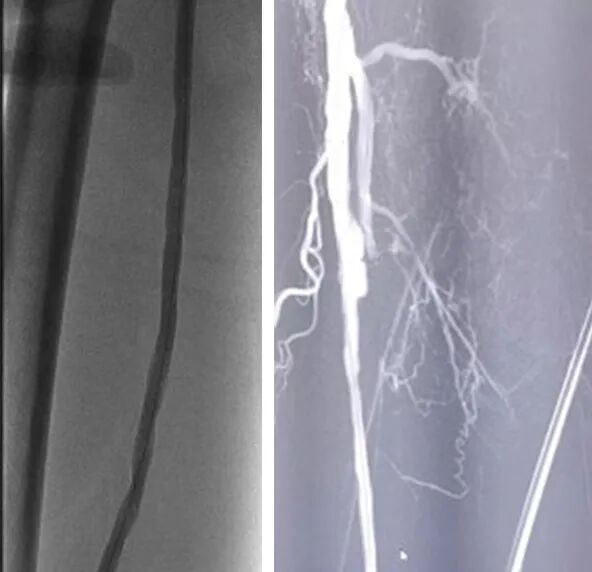

2、交换6F翻山鞘后,单弯导管配合导丝拟开通右股浅动脉病变,术中开通右股浅动脉近端时阻力较大,单弯导管配合泥鳅导丝下行距分叉5cm左右处下行困难,遂交换0.035系统支撑导管成袢下行通过。

3、0.018系统导丝建立工作路径后,予以3/4mm长球囊预扩张右股动脉病变,发现股浅近端造影剂滞留现象。

6、术中对于血栓组织予以直视下取栓,股浅动脉近端分叉病变予以内膜剥脱成形,股浅动脉远端病变予以置入Smart裸支架6*150mm、6*100mm,对于股浅动脉瘤予以缩窄缝合并将支架近端超过瘤样病变至少1cm,并予以5*150mm球囊后扩支架。